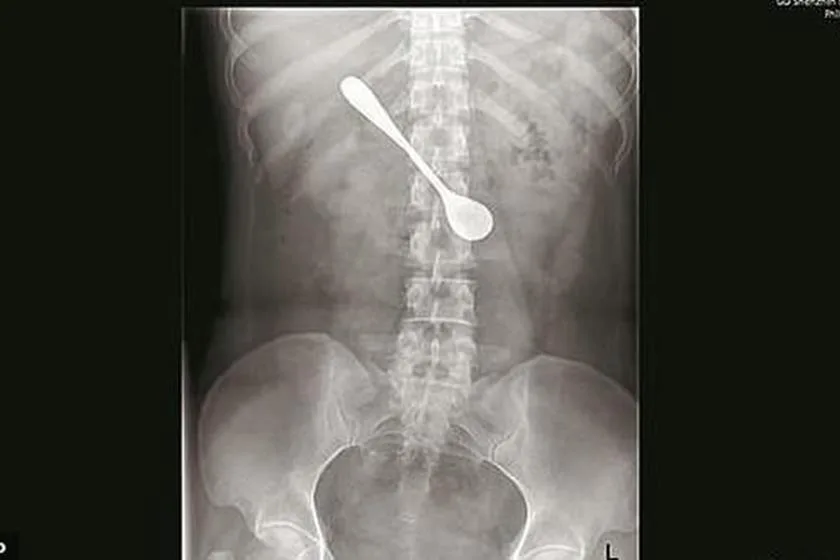

Uma mulher acabou, acidentalmente, engolindo uma colher de metal de 13cm ao tentar tirar uma espinha de peixe da garganta. O caso ocorreu na cidade de Shenzhen, China. Segundo informações da mídia local, a paciente, identificada apenas como Lili, ficou com o objeto no corpo por, pelo menos, quatro dias até ir ao médico.

Na unidade de saúde, a paciente fez um raio-X e passou por uma endoscopia. Segundo a jovem, ela não foi imediatamente para o hospital porque era feriado na cidade e os postos de atendimento estavam muito cheios. A paciente só procurou o médico depois de sentir dores no estômago.

Uma mulher da China engoliu uma colher de 13 cm

Segundo a jovem, ela tentava tirar uma espinha de peixe que estava na garganta

“Como a colher estava na posição horizontal, tivemos que ajustá-la antes de tirá-la do duodeno (o começo do intestino)”, disse o médico Sun Tingji ao jornal Daily Mail. Todo o processo durou 10 minutos. A espinha de peixe saiu por vias naturais.